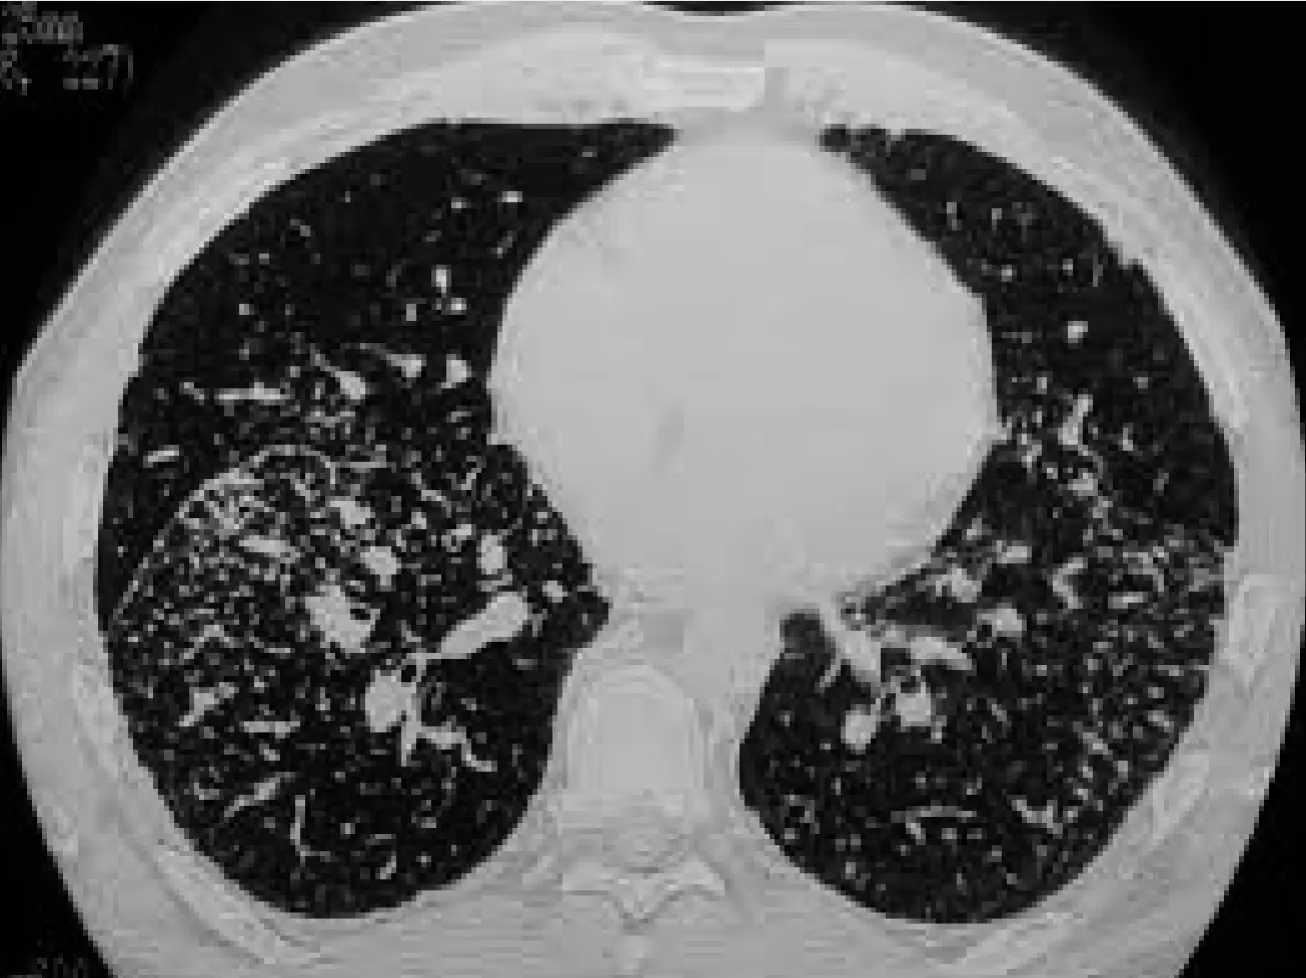

Chest X-rayx

- Bilateral hilar lymphadenopathy, interstitial changes.

Staging of Sarcoidosis on the Basis of Chest Radiographs

| STAGE | Description | Frequency |

|---|---|---|

| STAGE 0 | No abnormalities | 5%–10% |

| STAGE 1 | Lymphadenopathy (fig. A) | 50% |

| STAGE 2 | Lymphadenopathy + pulmonary infiltration (fig. B) | 25%–30% |

| STAGE 3 | Pulmonary infiltration (fig. C) | 10%–12% |

| STAGE 4 | Fibrosis | 5% (up to 25% during the course of the disease) |